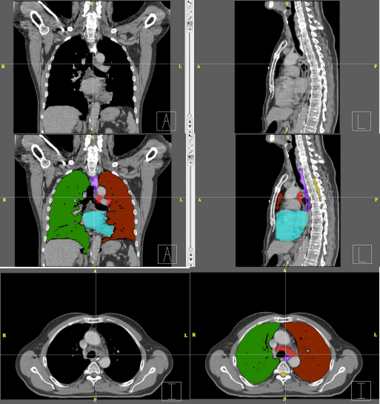

This example shows anatomic change in the thorax. The patient has a collapsed left lower lobe in the pre-treatment scan (top), which has recovered in the mid-treatment scan (bottom). Notice there is some kind of fluid accumulation below the collapsed lung.

Below are examples of segmentations of targets and critical structures for head and neck, and thorax. These structures (or similar) would be manually delineated for every patient who gets 3D planning.